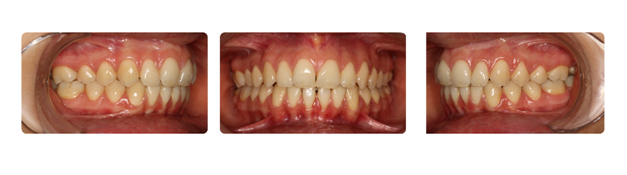

| دندانهای فک بالا و پایین دارای بی نظمی میباشند و با توجه به نبود فضا, بدون کشیدن دندان و توسط سیستم دیمون درمان میشوند: |

![]() |

| درمان با براکتهای دیمون نتیجه بخش است: |